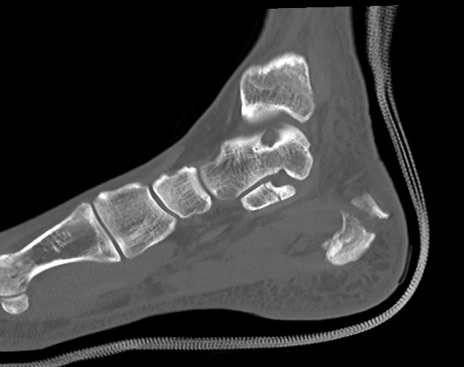

症例37 左足関節CT(矢状断像)

左足関節CT